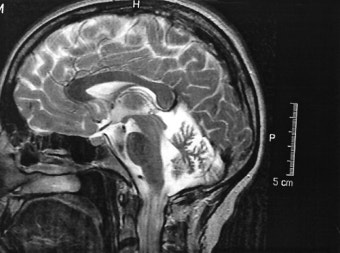

7. 진단 방법

확진은 쉽지 않습니다.

주로 아래 방법을 사용해요:

- MRI 검사

- 신경학적 검사

- 자율신경 검사